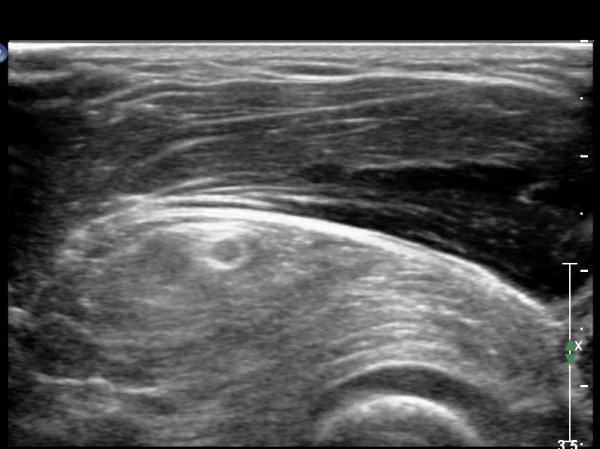

ŽÃËÀÚ¸¦ Á¶±Ý ¸»´ÜÀ¸·Î À̵¿ÇÏ´Ï ¿ä°ñµÎ°¡ °üÂûµÇ°í ÀÌÁú¼º°í¿¡ÄÚÀÇ Á¾±«°¡ Èİñ°£½Å°æÀ» Ç¥ÃþÀ¸·Î ÀüÀ§½ÃŰ´Â ¾ç»óÀ¸·Î °üÂûµÊ(»çÁø 2).